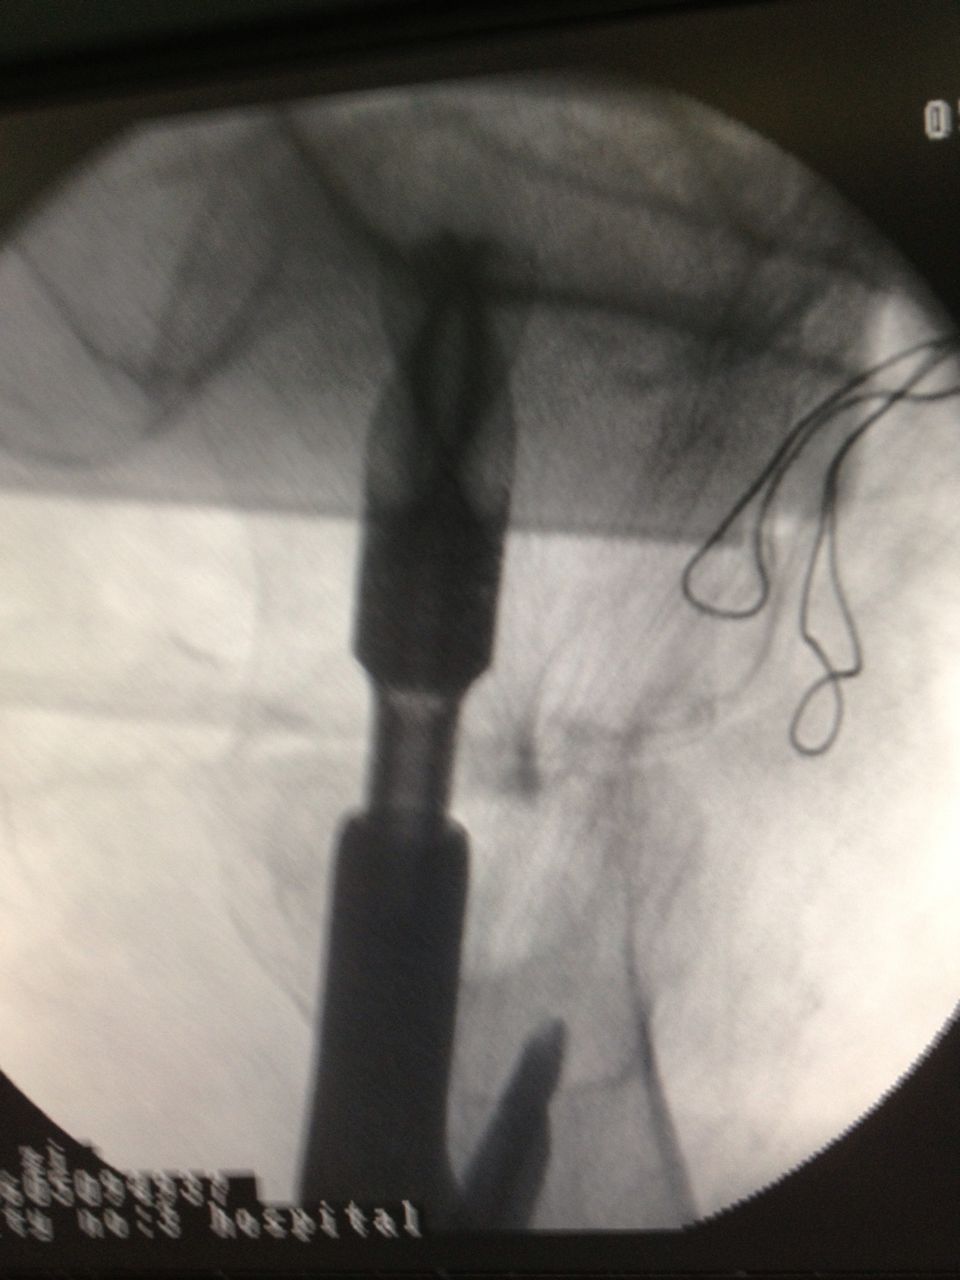

老人应选择何种治疗方案?第三医院骨科、心内科、麻醉科等多科专家组成的专家组认真仔细分析病情,决定采用髋关节微创植入内固定术。6月4日,老人接受手术,在手术牵引床上,通过C臂X光机透视,不切开骨折端闭合牵引复位,在老人骨折处复位到最佳状态时,刘忠国在骨折处开出5公分的口进行螺旋刀片动力髋固定,最大程度减少手术损伤,促进骨折端提早愈合。